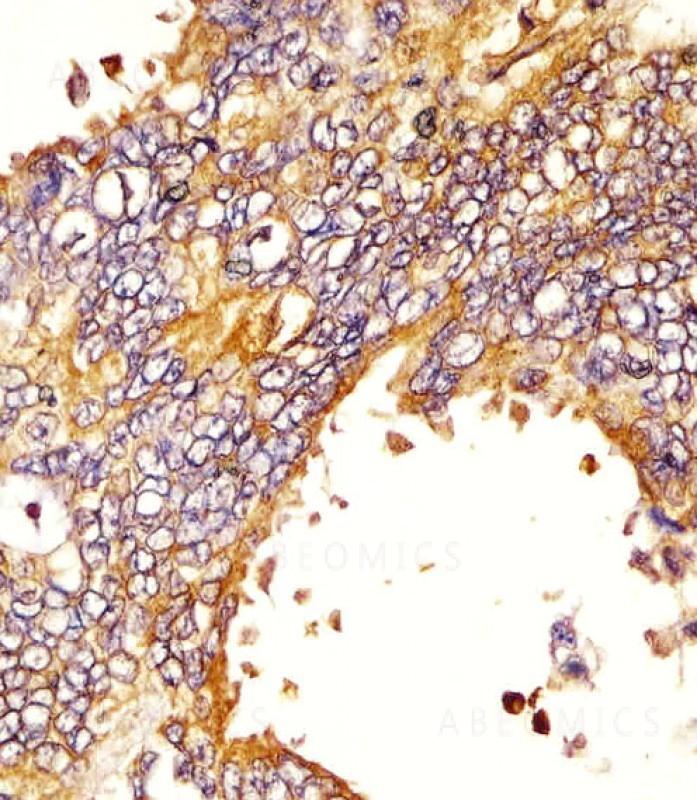

Figure 1: Staining of EGFR antibody (10-6607) in human lung adenocarcinoma sections by Immunohistochemistry (IHC-P - paraformaldehyde-fixed, paraffin-embedded sections). Tissue was fixed with formaldehyde and blocked with 3% BSA for 0. 5 hour at room temperature; antigen retrieval was by heat mediation with a citrate buffer (pH6). Samples were incubated with primary antibody (1/25) for 1 hours at 37°C. A undiluted biotinylated goat polyvalent antibody was used as the secondary antibody.